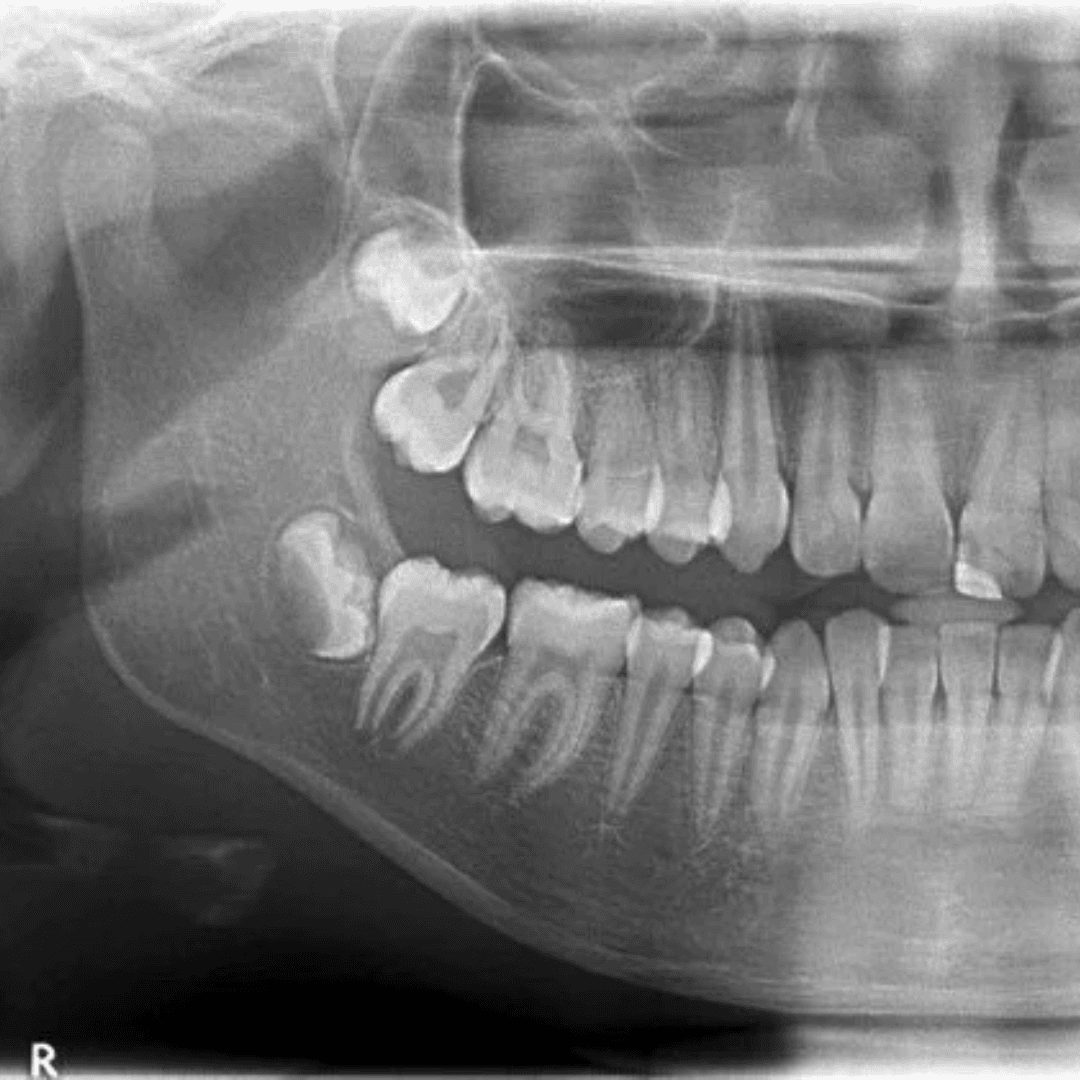

A panoramic X-ray gives a wide overview of your teeth, jaws and supporting bone. It’s often used before:

• Wisdom teeth checks (wisdom teeth info)

• Reviewing gum health signs: bone levels, loose teeth (overview) — see gum disease

Wisdom teeth and jaw checks

A broad overview that can support wisdom tooth assessment. If you’re considering removal, see wisdom tooth extractions.

Clinics commonly request an OPG for planning veneers, crowns, implants, and All-on-4. The scan helps with an overview of the current dentition, visible bone levels, jaw anatomy, and broad assessment of key areas.